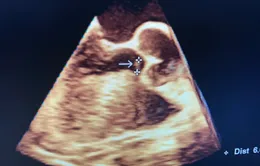

VTV.vn - Cụ ông 70 tuổi ở Nghệ An được cứu sống trong tình trạng khó thở tăng dần, đau tức ngực do dịch gây ép tim nghiêm trọng ảnh hưởng đến tính mạng.